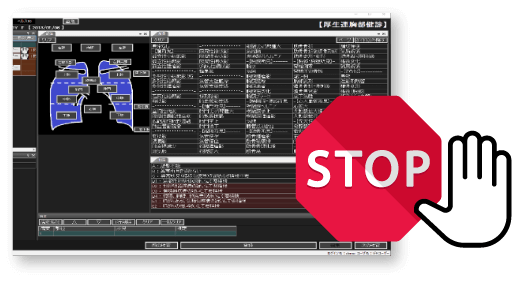

事務業務の人的ミス・負担を軽減したい!

- 連番撮影のマッチングを自動化し、作業時間を大幅削減

- ボタン一つで二重読影結果を統合。数秒で最終結果確定へ

- 画像登録から結果出力までの進捗状況を、一覧画面で簡単に確認

- 基幹健診システムと連携することで、結果の転記も不要

二重読影結果の一括自動判定

判定結果を色分表示

読影の進捗状況を一覧画面で管理

健診種別を細かく設定して管理可能

煩雑だった業務が数秒で完了!

人的ミスや業務スタッフの負担を大幅に軽減します。